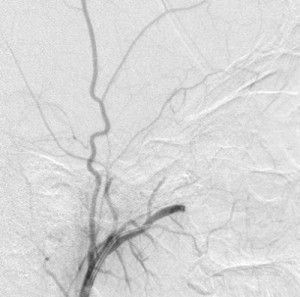

Fourth panel, left to right: Digital subtraction angiogram of the left internal maxillary artery before (1st two images, a frontal and a lateral view of the face) and after embolization (the last image, a lateral view). (For the 2nd and 3rd images, assume the patient’s face is turned to your right). Note the intense blushing of the tumor before embolization emphasizing its vascularity. Following embolization the mass is invisible.

Severel treatment options for JNA have been described in the literature, some now obsolete. They include hormonal therapy (the tumor has receptors for many male hormones), radiation, embolization, chemotherapy, open surgical removal, and, in the last 2 decades, endoscopic resection of the mass. Hormonal therapy is largely abandoned for its ineffectiveness. Radiotherapy has been applied as definitive treatment for advanced JAN and has local control rates between 85% and 91%. However, it may be complicated by panhypopituitarism, growth retardation, cataracts, radiation keratopathy, temporal lobe necrosis, and malignant transformation of the tumor, especially with high doses of radiation. It is perhaps excellent in treating primary or recurrent disease in critical areas, where surgical excision of the tumor may be hazardous. Open surgical extirpation was the only method of resecting the disease before the advent of modern novel techniques like endoscopic resection and radiofrequency coblation. There are many approaches to resecting the disease each dependent on the location and extent of the tumor. It is sometimes combined with endoscopic resection. Bland embolization of JNA is ususally offered as a presurgical intervention to limit hemorrhage during surgical removal. The usual arterial source to the tumor is the internal maxillary artery, but it may receive branches from the ophthalmic artery, ascending pharyngeal artery, and the facial artery. Identifying and embolizing these sources reduces the amount of intra-operative blood loss by 50% or more and creates a relatively bloodless operating field that improves tumor resection. When embolization is offered, surgical resection should be done in 2 to 5 days to avoid the development of collateral supply to the tumor. Endoscopic resection of the tumor enjoys certain advantages over traditional open surgery: comesis (no facial scars), shorter hospital stay that translates to lower cost; shorter recuperation; and better or equal recurrence rate. However, there are controversies over what stage of the disease is best treated by this technique. (I have eliminated the staging of JAN in this writing for want of space.)

His laboratory investigation was unremarkable and the tumor was successfully resected endoscopically following presurgical embolization of his terminal left internal maxillary artery; the estimated blood loss was 350 mL. He did well following surgery but defaulted on followups. This month celebrates his first year of the resection of the tumor.